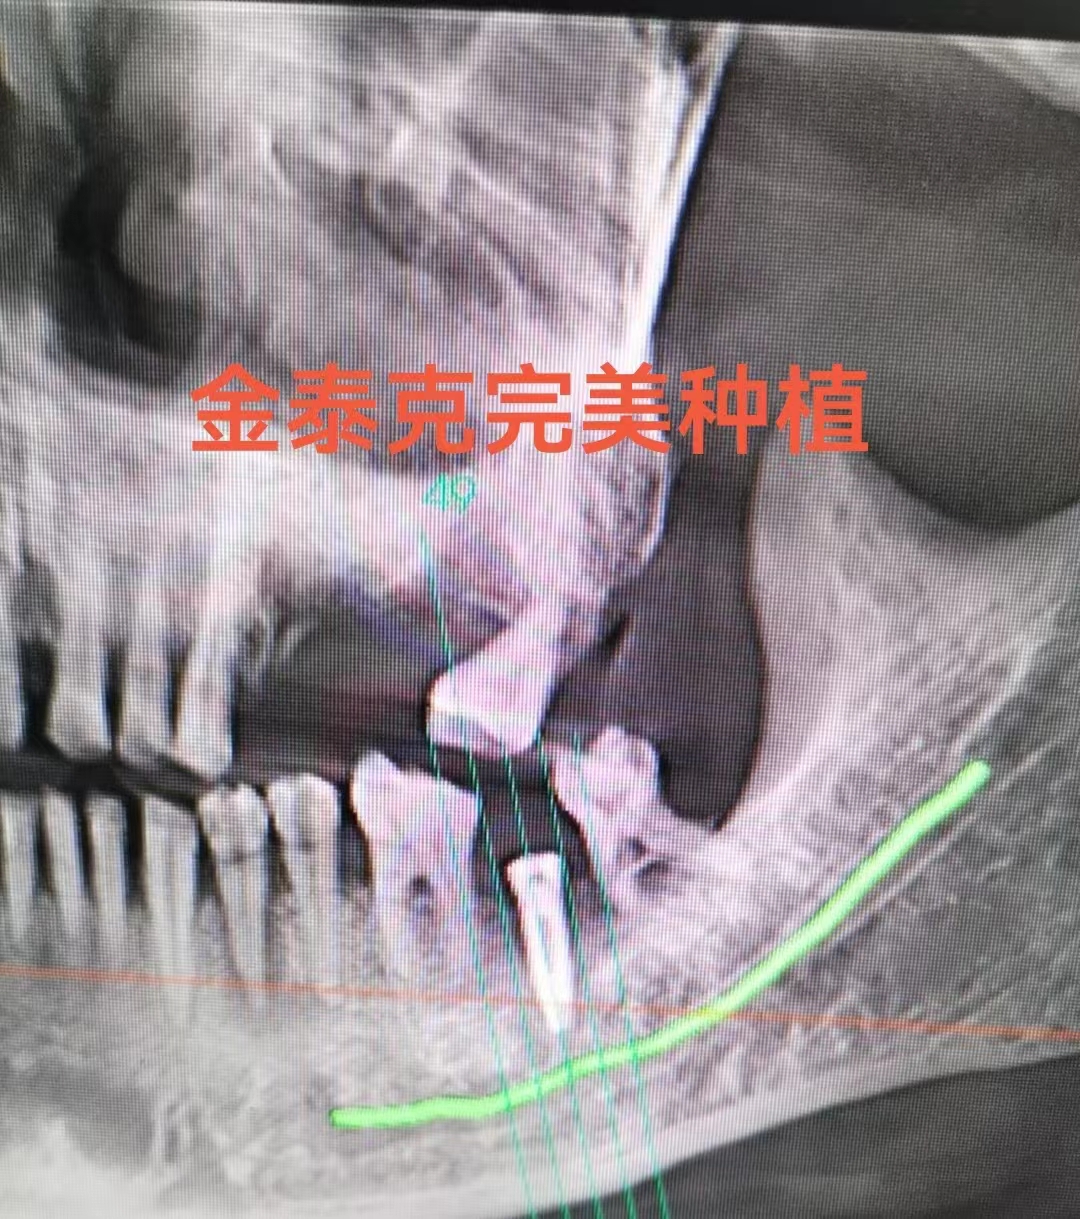

來自孟加拉達(dá)卡大學(xué)Mendy牙學(xué)院的Azad院長和印度德里最好牙學(xué)院(Maulana 牙學(xué)院)的Kumar教授(前任南亞牙醫(yī)師協(xié)會主席)由海外飛到徐州參觀金泰克公司的現(xiàn)代化的種植牙生產(chǎn)基地,對金泰克的生產(chǎn)技術(shù)給予了高度的認(rèn)可并堅(jiān)定了對金泰克高品質(zhì)種植牙的信念。此外張杰博士在門診親自給兩位來賓現(xiàn)場展示了金泰克10分鐘微創(chuàng)無痛種植牙手術(shù),手術(shù)的流暢操作和病人對手術(shù)的極高滿意度給來訪的嘉賓留下了深刻的印象,并明確表示要把金泰克產(chǎn)品和微創(chuàng)無痛技術(shù)引進(jìn)到印度和孟加拉,推動本地的惠民口腔種植事業(yè)。